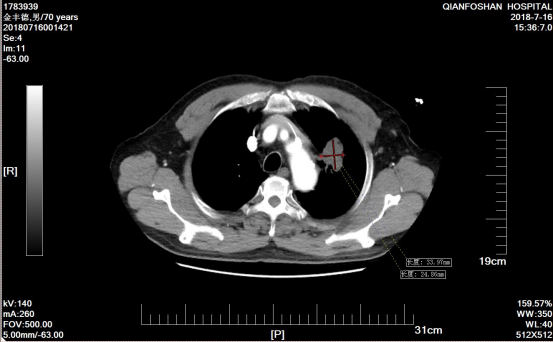

李老伯术前肿瘤CT影像图经过李老伯的子女辗转打听,在确诊一周后李老伯便来到山一大一附院。“肺鳞癌又称肺鳞状上皮细胞癌,是我国最常见的肺癌类型之一,多见于老年男性,与吸烟有密切关系。”医院肿瘤微创科主任医师刘元水表示,众所周知,手术、放疗、化疗被称为癌症治疗的三板斧。因为发现较晚,患者左肺部肿瘤达6.4cm x 5.3cm并侵犯了主动脉弓,已经失去了手术指征,且肺鳞癌对放疗、化疗不敏感,治疗效果有限。